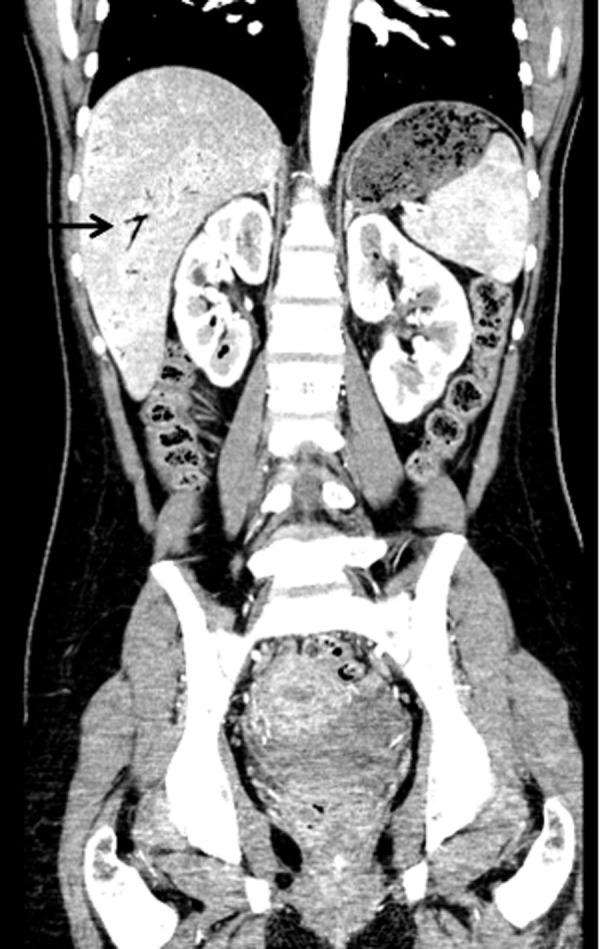

Emphysematous gastritis with portal venous air is a rare condition usually caused by gas forming organisms. This may be secondary to local spread of an infection through the mucosa or rarely hematogenous dissemination from a distant focus. We present a young diabetic woman with uncontrolled diabetes mellitus who was admitted with sepsis and severe abdominal symptoms. Investigation revealed emphysematous pyelonephritis due to E. coli infection associated with emphysematous gastritis and air in the portal tract. She improved with broad spectrum antibiotics, fluid resuscitation and electrolyte and diabetic management. To our knowledge this is the first report showing the association between emphysematous pyelonephritis and gastritis with air in the portal system.